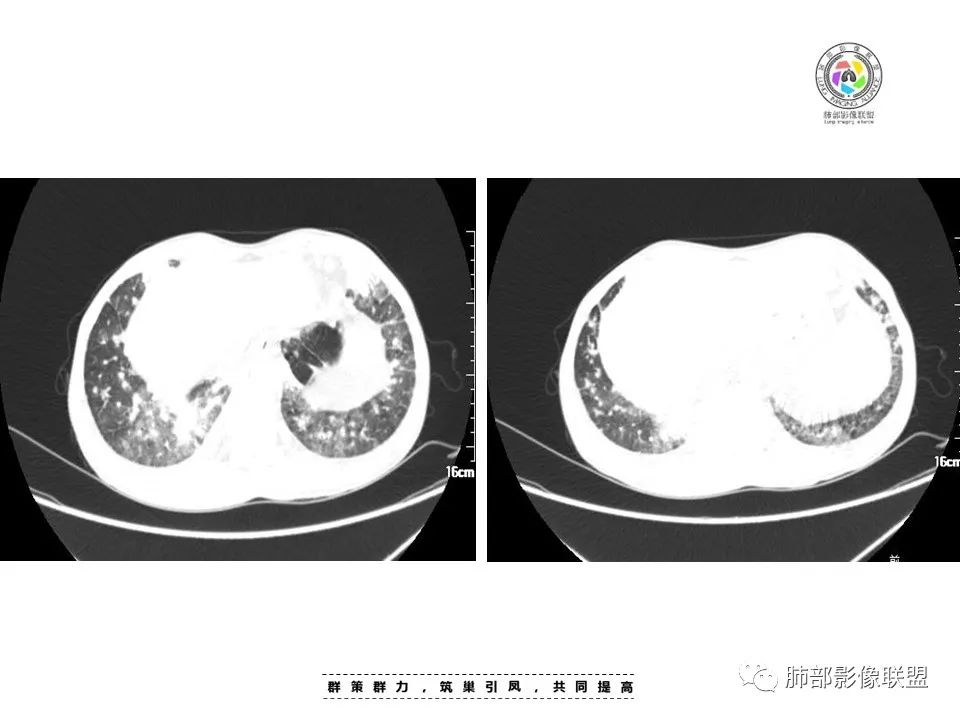

中年男性,发热、纳差、乏力、皮疹1月,,全身散在暗紫色丘疹,CD4明显减少,双肺散在多发斑片状、结节状密度增高影,边缘稍模糊,以双肺下叶较多,沿支气管血管束播散征象,小叶间隔增厚,叶间裂及双重胸膜腔少量积液,考虑马尼可能大,建议真菌,比如曲霉?念珠菌等

周一晚读病例:男性45岁,发热、纳差,全身散在暗紫色皮疹,结合CD4,符合HIV;肺部影像表现:两肺散在实性结节及磨玻璃密度影,实性结节伴晕征,部分沿支气管血管束分布,支气管血管束增粗,以两肺下叶为著,类似火焰征,双侧胸腔少量积液;首先考虑卡波西肉瘤,鉴别淋巴瘤增值性病变,淋巴瘤样肉芽肿/淋巴瘤,最后挂上马尔尼菲青霉菌病。

两肺多形态小斑片影,上轻下重沿支气管血管分布,双肺下叶小片状,密度不均匀,含模糊的GGO影,右肺中、下叶与左肺舌叶及下叶病灶累及中轴及小叶间隔增厚,双肺叶间胸膜增厚及伴随粟粒结节,双侧胸腔对称性少量积液,纵隔脂肪间隙混浊(示淋巴回流受阻),慢性发病,发热,乏力,皮肤皮诊表现,贪血,WBC,CD4+低,脾增大,肺感染疾病:马尔尼菲篮状菌,并发TB待排,支气管镜肺泡灌洗液和结核X-Pert检查。

中年男性,发热、全身散在暗紫色丘疹,查CD4+T细胞64个/ul,临床信息提示AIDS并发卡波西肉瘤;CT提示双肺多发实性结节影及毛玻璃结节,部分呈点晕征,右上肺大姐姐边缘膨隆、分叶伴晕;双下肺结节沿支气管血管束分布,中轴间质增粗,部分支气管堵塞,叶间裂结节状增厚,部分结节胸膜下分布,可疑局部小叶间隔增厚,肺部病变呈淋巴分布特点,结合临床肺部病变考虑肺卡波西肉瘤,鉴别淋巴瘤。

两肺弥漫性性结节状、小片状及片状带晕的病灶,煎蛋征、点晕征,主要分布两肺中下叶,病灶周围小叶间隔增厚呈网格状影,部分病灶累及胸膜,伴两侧胸膜增厚。

2.本例双肺小叶间隔增厚明显,多发结节影及片状实性密度影,沿血管支气管束分布为主,两侧较为对称,病灶多环以磨玻璃晕,边界不清。

双侧胸腔少量积液。双肺门及纵隔未见明确肿大淋巴结,纵隔结构间隙模糊。

3.有学者将这种具有沿双肺支气管束分布的实性密度片影描述为“火焰征”,认为具有一定特征性,单就影像表现而言,这种影像表现也可以见于其他病损或多种病理改变的叠加。

如马尔尼菲篮状菌感染,HIV患者总会联想到它!同样可以出现双肺多发结节影、片影及磨玻璃影,结节影边界也可以较为清楚(甚至可以有点类似结核那种肉芽肿结节),磨玻璃影常见于灶周出血等等。尽管临床实践中马尔尼菲篮状菌感染似乎更多表现为淋巴增大及网质内皮系统损害(如肝脾改变)以及较特有的带有脐凹的皮疹等等。

4.患者病史发热、纳差、乏力、暗紫色皮疹一月,其中暗紫色皮疹对卡波西肉瘤的诊断具有一定提示意义。